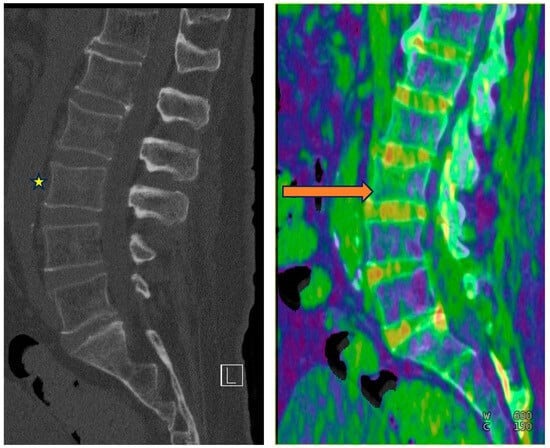

5.4. Examples in the Musculoskeletal System

5.4.1. Bone Marrow Edema (BME)

5.4.2. Gout